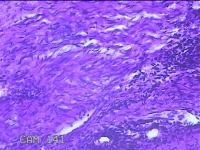

右侧卵巢囊肿

性别

女

年龄

19岁

临床诊断

一般病史

下腹痛1小时。

标本名称

大体所见

灰白暗红色囊壁样组织11x4.5x2.3cm两块,表面糜烂,因已切开,囊内容物已流失,囊壁厚0.1cm。